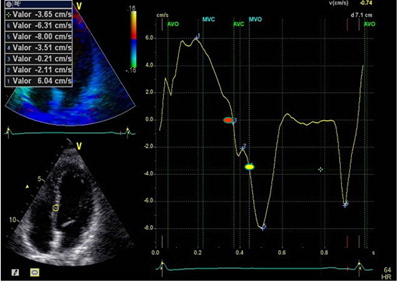

Figure 1: LVPPMC curve in a normal patient. The red dot indicates the beginning of the phase and the yellow dot its completion. Duration: 80ms; left ventricular mass: 67 gr/m2; relative wall thickness: 0.33%.

A significant increase of LVPPMC time was found in Group III patients with HFpEF compared with the group without heart disease (Group I and II). Moreover, in these cases the tissue strain curve loses its sharp slope and becomes irregular needing a more prolonged time to generate the necessary pressure difference to open the mitral valve (Figure 1 and 2). This variable correlates with the E/E’ ratio, since in Group I this was 6,34±1,46 compared with Group II that reached a value of 7,50±1,53 and the Group III which reached a value of 16.13±6.47 (p<0.01) (Table 1). An abnormal effect can be interpreted in the negative pressure generated in this phase, evidencing a delayed process with longer time to open the mitral valve [7] (Figure 1 and 2). We also observed that the diastolic duration (passive filling phase without energy consumption) was maintained with scant variation in all groups (354ms in the Group I; 471ms in the Group II and 333ms in the Group III), confirming that the altered suction mechanism occurring in the LVPPMC mainly participates of the dysfunctional process. The increase in LVM, RWT and VAI in Group III, all with significance, are measurements that correspond to an increase in PAP to 32mmHg in Group III in relation to Groups I and II of 22mmHg. These concepts would explain why in HFpFE a pulmonary wedge pressure ≥15 mmHg or a left ventricular end-diastolic pressure ≥16 mmHg is usually found [8]. The possible interpretation is that as the LV mass increases it does not reach suitable detorsion in a normal time to generate a drop in pressure with adequate slope to open the mitral valve.